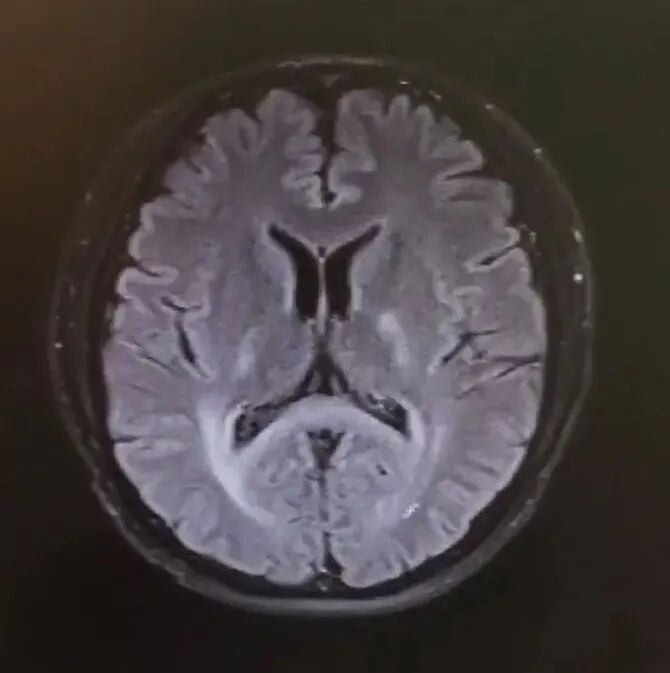

Y先生入院后,醫(yī)生給予完善核磁共振檢查,提示顱內(nèi)多發(fā)白質(zhì)異常信號(hào)以及頸段及胸段脊髓明顯變細(xì)。神內(nèi)二區(qū)主任常保強(qiáng)博士帶領(lǐng)的醫(yī)療團(tuán)隊(duì)根據(jù)患者發(fā)病特點(diǎn)、臨床癥狀、體征,肌電圖、血極長(zhǎng)鏈脂肪酸檢測(cè)、頭顱、全脊柱核磁共振等檢查,考慮遺傳代謝性疾病可能性大,于是給患者做了基因檢查,最終確診是成人型腎上腺腦白質(zhì)營(yíng)養(yǎng)不良,且為腎上腺脊髓神經(jīng)病型(AMN)。

頭顱MR-FLAIR相提示雙側(cè)內(nèi)囊后肢、雙側(cè)腦室后角周圍及胼胝體壓部白質(zhì)異常信號(hào)

與大多數(shù)AMN患者相似,該例患者于40歲前發(fā)病,以典型的痙攣性截癱為突出表現(xiàn),影像學(xué)顯示脊髓明顯萎縮變細(xì),而顱內(nèi)可見非特異性的白質(zhì)病變,結(jié)合極長(zhǎng)鏈脂肪酸和基因檢測(cè)結(jié)果,確診為AMN。

目前僅單純從臨床上很難鑒別導(dǎo)致雙下肢行走困難的原因,必須借助測(cè)定極長(zhǎng)鏈脂肪酸C26與其他極長(zhǎng)鏈脂肪酸的比值以及基因檢測(cè),判斷是否存在腎上腺腦白質(zhì)營(yíng)養(yǎng)不良。該患者病程較長(zhǎng),曾被診斷運(yùn)動(dòng)神經(jīng)元病,但近2年來(lái)出現(xiàn)上運(yùn)動(dòng)神經(jīng)元受損的癥狀體征和脊髓萎縮,且頭顱MR存在雙側(cè)對(duì)稱性白質(zhì)異常信號(hào),均不支持該病的診斷。